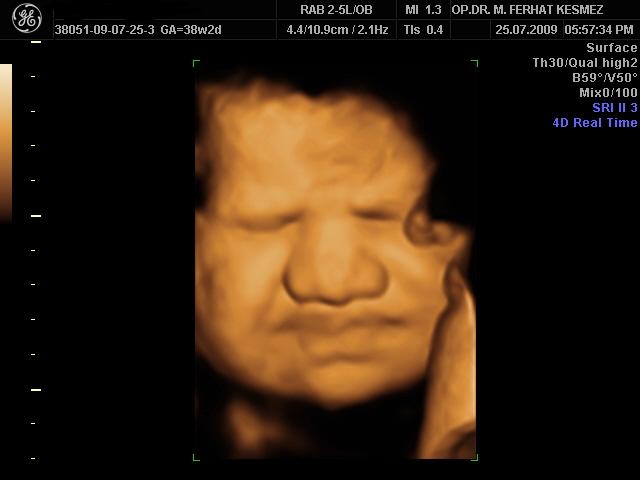

4 Boyutlu Ultrason